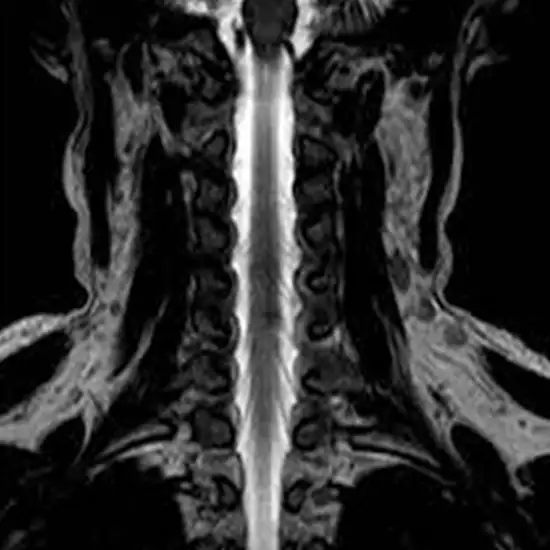

MRI Myelogram is an imaging test to take a detailed image of the spinal cord, nerve roots, subarachnoid space, and spinal column. It includes inserting a spinal needle into the spinal canal and injecting contrast material into the subarachnoid area. It is also known as MRI Myelography.

• The most frequent use of MRI myelogram is to identify anomalies in the spinal cord, spinal canal, spinal nerve roots, and blood vessels supplying the spinal cord.

• It is used to demonstrate whether a herniated intervertebral disc between the following vertebral bodies is squeezing the spinal cord or nerve roots.

• To illustrate spinal stenosis is a disorder that frequently results from the deterioration of the bones and soft tissues around the spinal canal. Due to the growth of bony spurs (osteophytes) and the thickening of the surrounding ligaments, the spinal canal becomes smaller as the surrounding tissues become larger in this disorder.